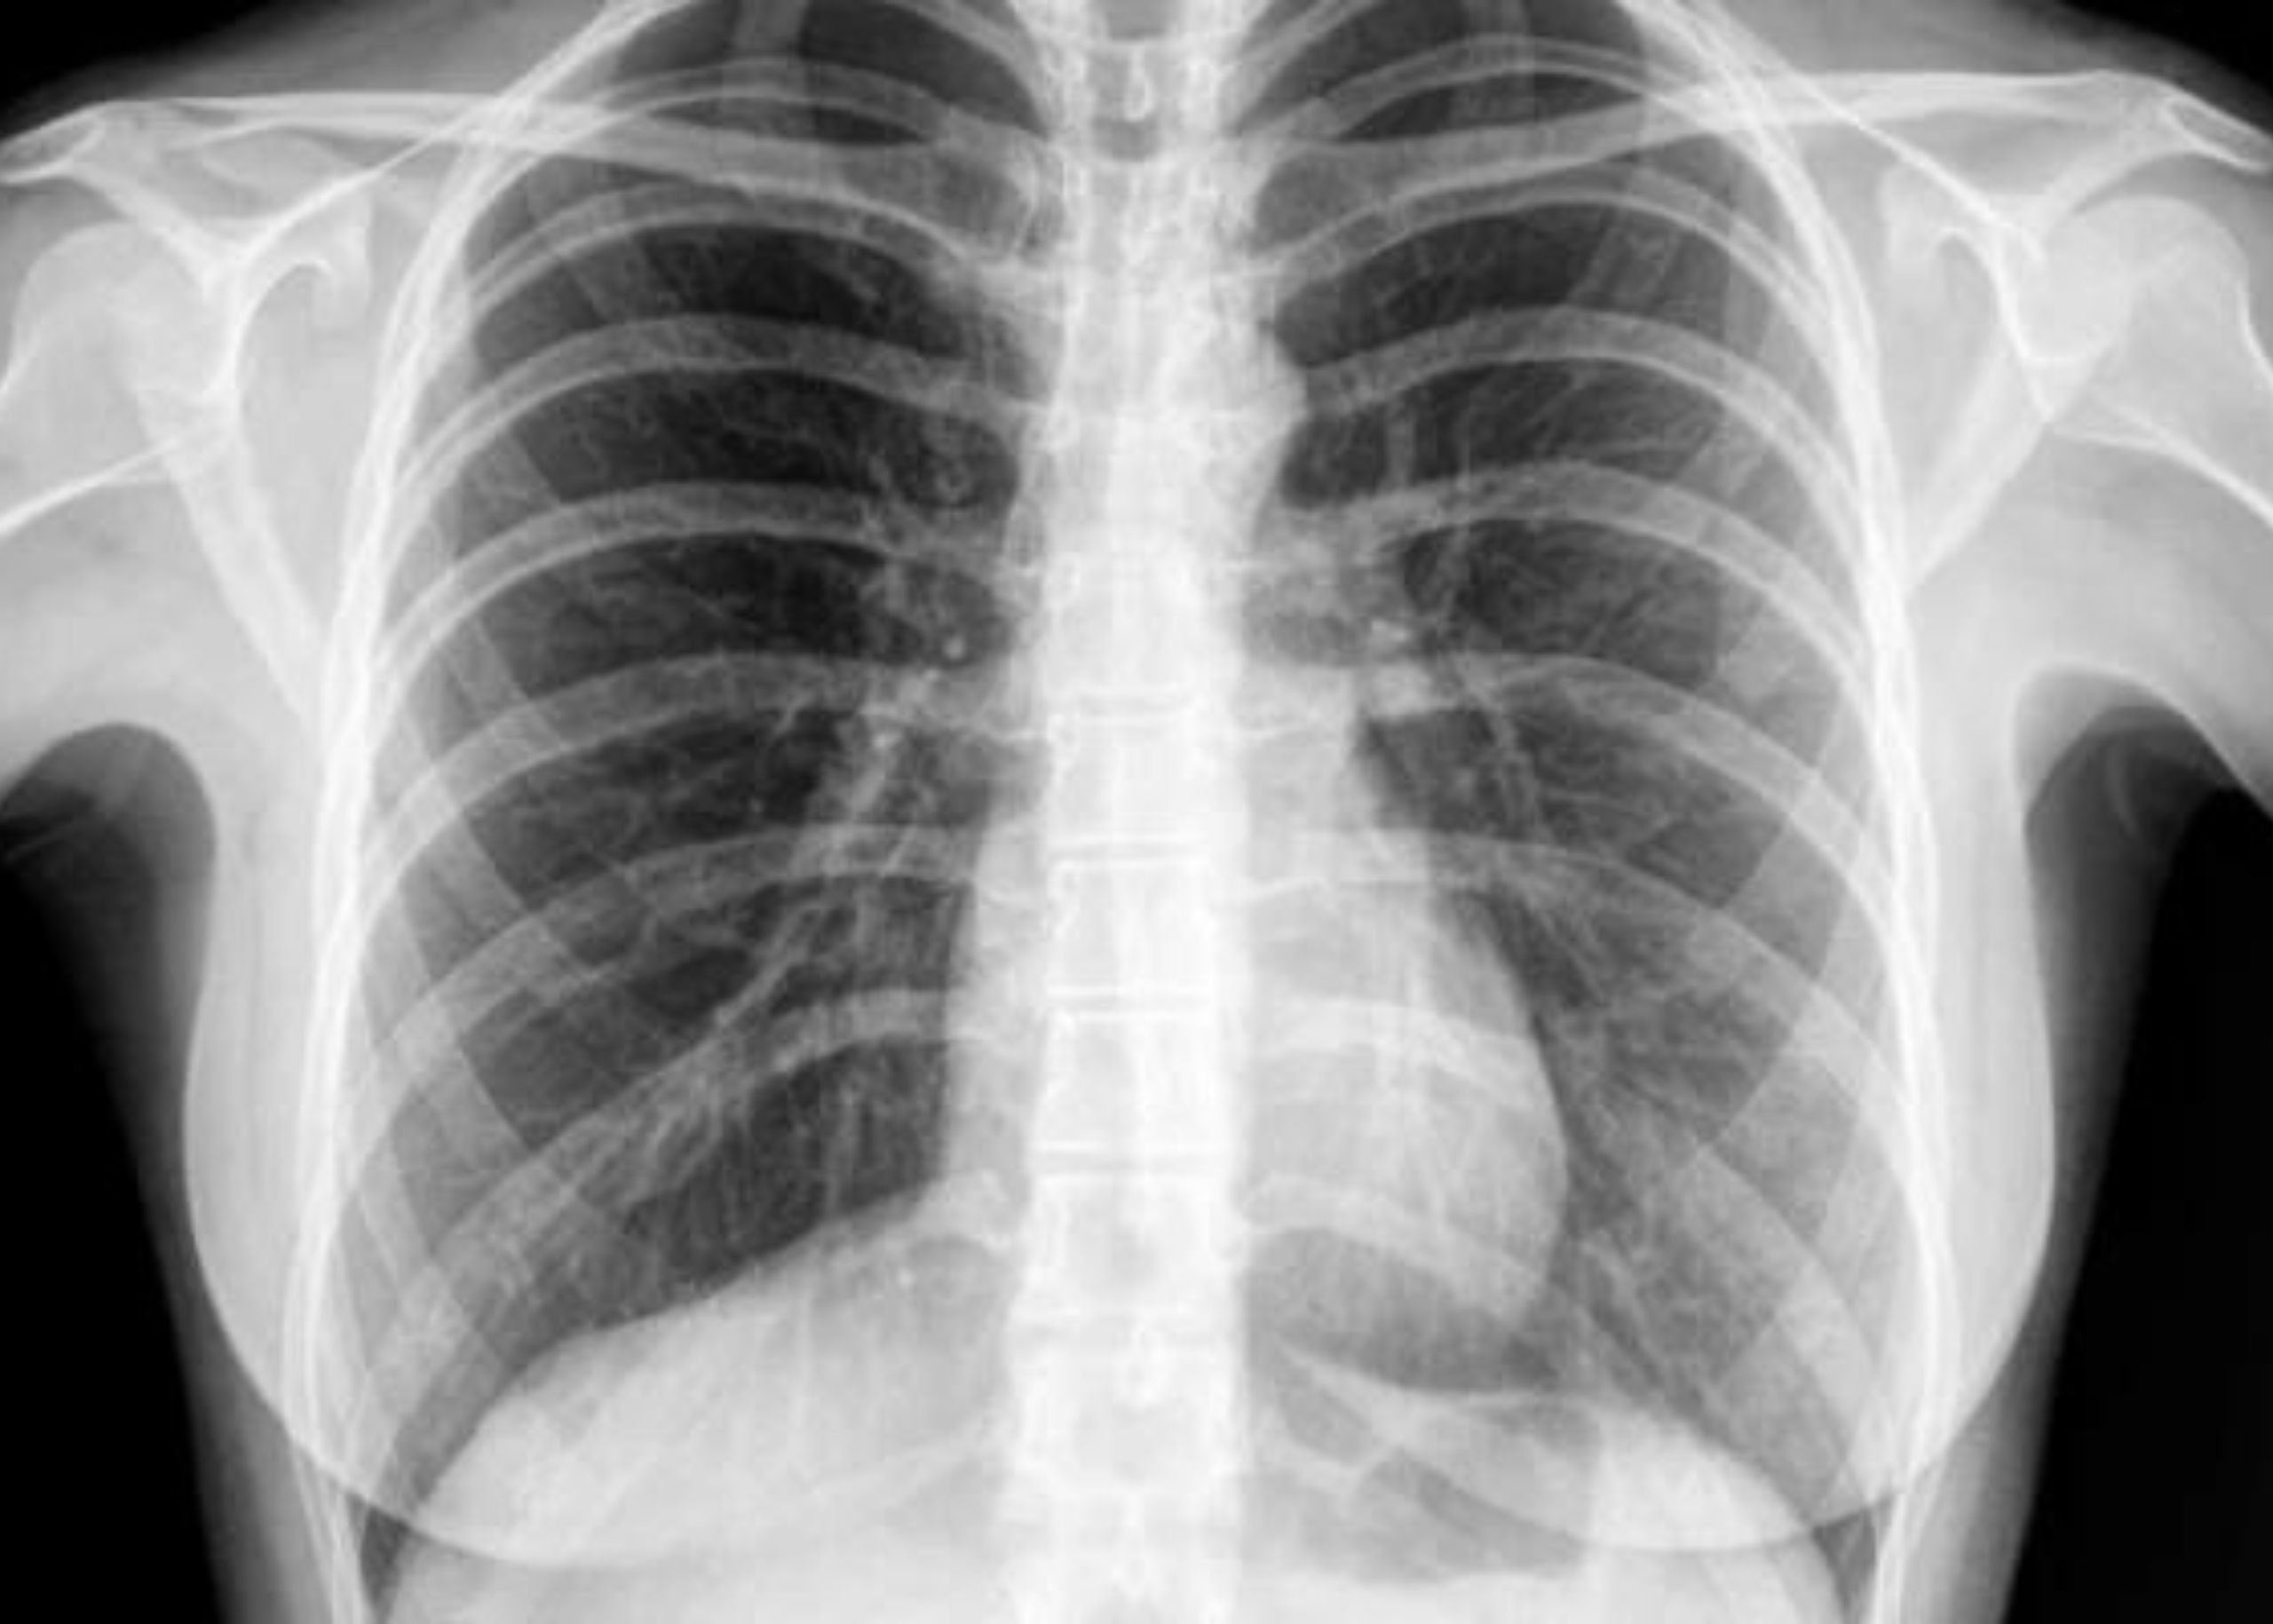

Respiratory diagnostic testing

Modern diagnostic tools for accurate assessment